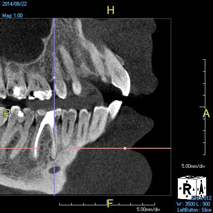

(8.) An original finding of a small lesion on the mesial root of tooth No. 30 was not accompanied by any outward symptoms; therefore, the patient delayed pursuing treatment. When a follow-up CBCT scan was acquired 6 years later, the easy-to-visualize increase in the dimensions of the lesion motivated the patient to elect a treatment plan.

Figure 8

(9.) An original finding of a small lesion on the mesial root of tooth No. 30 was not accompanied by any outward symptoms; therefore, the patient delayed pursuing treatment. When a follow-up CBCT scan was acquired 6 years later, the easy-to-visualize increase in the dimensions of the lesion motivated the patient to elect a treatment plan.

Figure 9